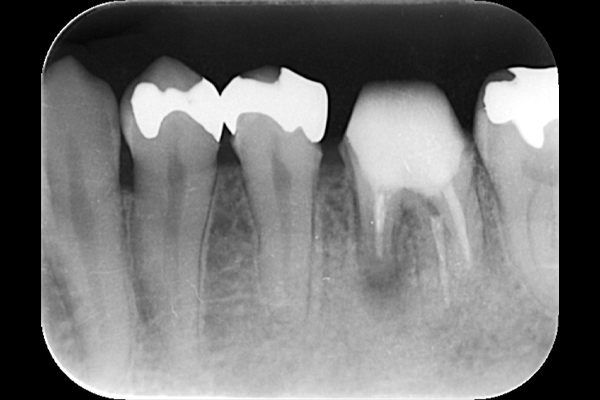

それは歯の先に枝分かれが多く存在し、そこにばい菌が入り込んで難治性となっているからです。ではその場合どうするのか?外科治療をします。その枝分かれの部分を切り落とすのです。今回はその前後のレントゲンの写真をお見せします。

| 根の中の薬が十分に充填されておらず、根の先が周りと比べて黒くなっており、炎症があると判断できます。 | 根の中にしっかりとお薬を緊密に充填しましたが、まだ根の先に黒くなっている部分があります。 |